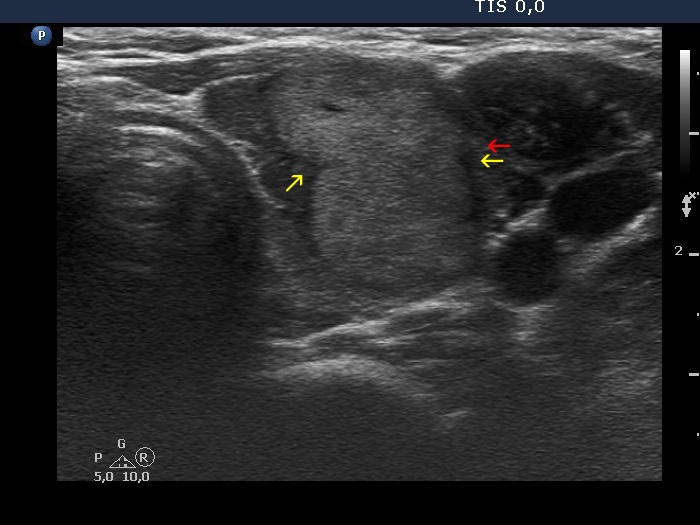

The borders of the nodule - case 479 (ultrasonographic picture 3b)

Left lobe, transverse view. A protrusion is marked with red arrow. The cause for this protrusion is more likely the infiltration the isoechoic lesion by the underlying thyroiditis (yellow arrows) and not the infiltrative nature of the isoechoic lesion.